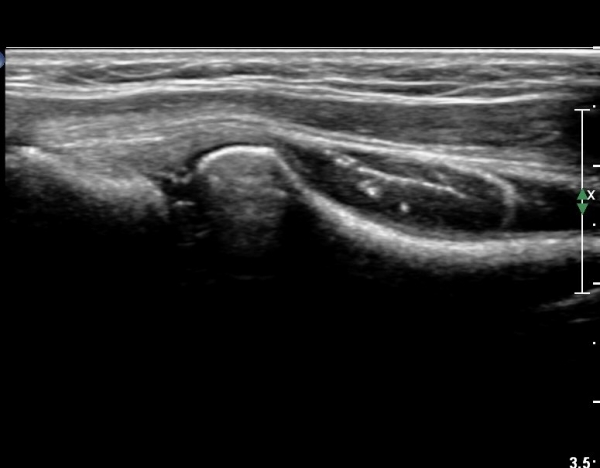

¿Ü»ó°ú¿¡¼­ ¼Õ¸ñ ½ÅÀü°Ç ´ÜµÎ Á¾´Ü¸é°Ë»ç¿¡¼­ ƯÀÌ ¼Ò°ßÀ» º¸ÀÌÁö ¾Ê´Â´Ù(»çÁø 1, 2)